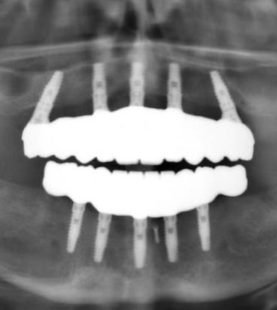

Periodontal Grafting and Crown Lengthening Surgery

- Diagnosis protocols

- Posterior and Anterior crown lengthening

- Achieve Precision in Anterior and Posterior Crown Lengthening

- Learn advanced techniques for crown lengthening in both anterior and posterior regions, addressing anatomical challenges and improving the esthetic and functional outcomes of restorative dentistry.

- Gain the ability to assess and plan crown lengthening procedures for complex cases involving tooth structure or soft tissue discrepancies.

- Learn how to integrate diagnostic protocols, including clinical evaluation and radiographic assessment, to support effective treatment planning.